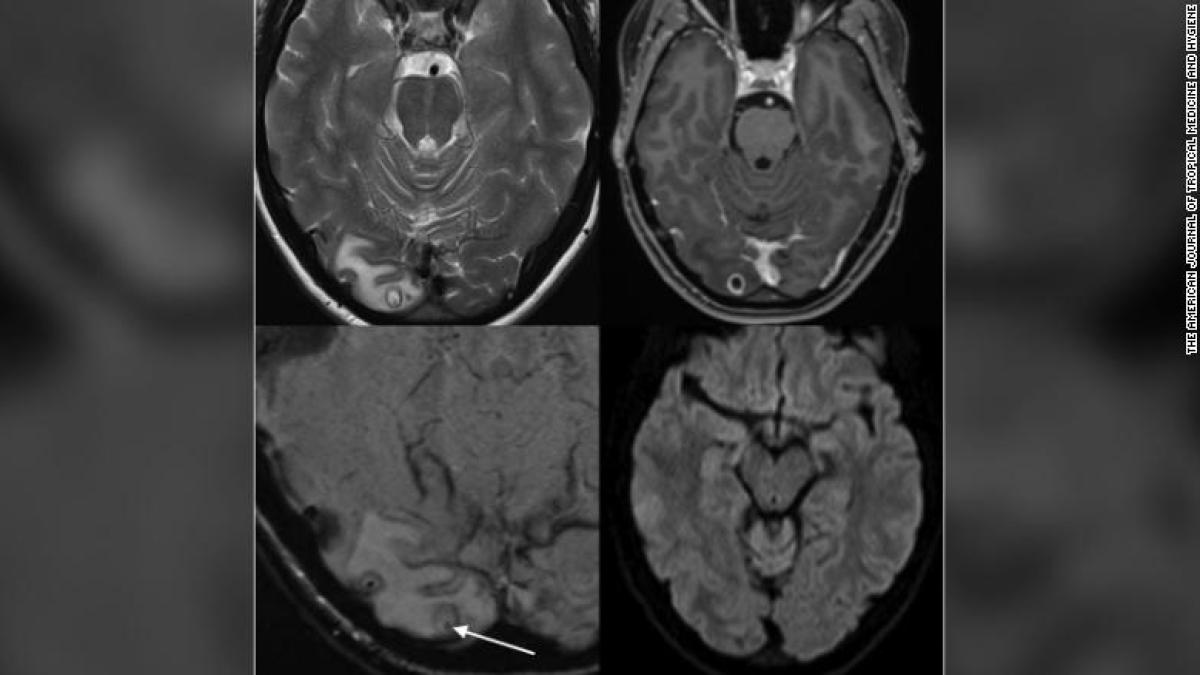

Medicii au supus-o unui examen RMN și au crezut că au de-a face cu o tumoră, dar după ce au operat și îndepărtat leziunea, au descoperit că este de fapt un chist plin de larve de tenie. După îndepărtarea chistului nu a mai fost nevoie de niciun tratament.